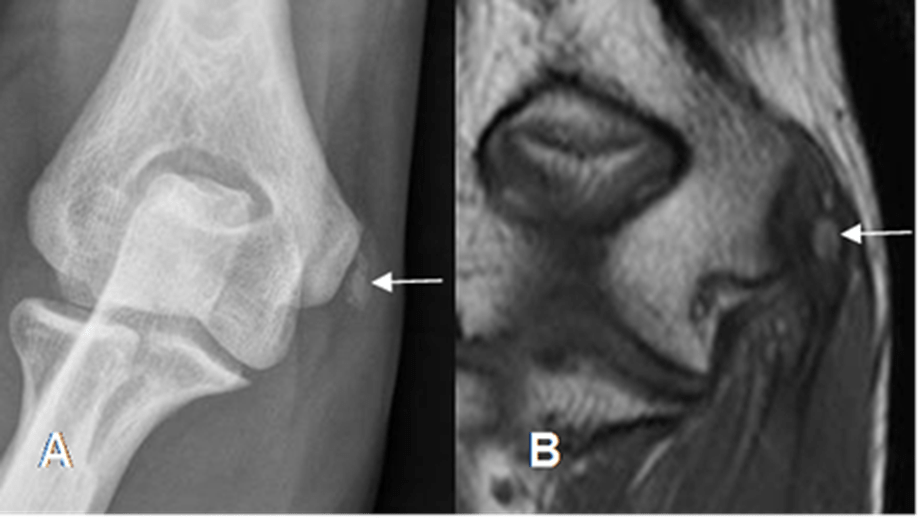

Epicondilitis

Epicondilitis medial.

A: Rx AP y B: RM coronal en T1. Calcificación sobre el origen de los tendones flexores, por tendinitis crónica.

Aunque es un diagnóstico clínico (codo de tenista o de golfista), en casos persistentes puede pedirse radiografía para descartar calcificaciones o lesiones óseas.